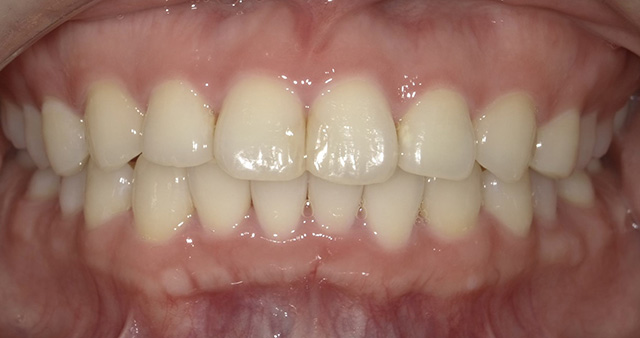

「歯並びを治したい」という目的は、見た目の改善が大きな要素を占めますが、矯正治療はそれ以上のメリットをもたらしてくれます。見栄えがきれいになることに加え、しっかり噛むことができるようになるため、食べ物の消化を効率的にしたり、歯みがきもきちんとできるようになるため、むし歯や歯周病にかかりにくくなったり、正しい発音でしゃべることができるようにもなります。

現在の矯正歯科の治療技術は進歩しており、成人の方でも無理なく矯正治療を行えるようになっています。確かに、お子さんの方が成長期にあるためスムーズに治療を行うことができますが、成長期以降の成人の方でも、多少時間はかかるものの、歯並びや噛み合わせのお悩みを解決することは可能です。矯正の大きな目的には、見た目のコンプレックスの解消がありますが、そのほかにも、きれいな歯並びになることで、歯みがきがしやすくなり、むし歯や歯周病の予防につながります。また、噛み合わせが整うことで、筋肉や顎関節、歯周組織に余計な負担をかけずにすみ、全身の健康にもつながります。

健康的で美しい口元になって、明るい笑顔で毎日を過ごしましょう!